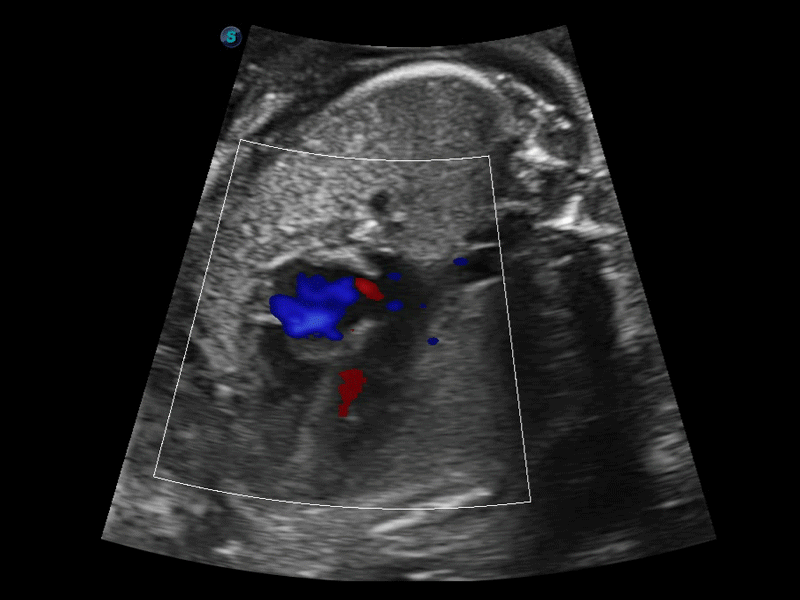

S-Fetus 产科扫查助手

S-Fetus基于大数据深度学习算法,能够帮助您在产前筛查过程中智能识别胎儿标准切面、自动测量并录入报告。一个按键,即可智能、精准、高效地获取胎儿生理指标,极大简化您的产科检查操作。